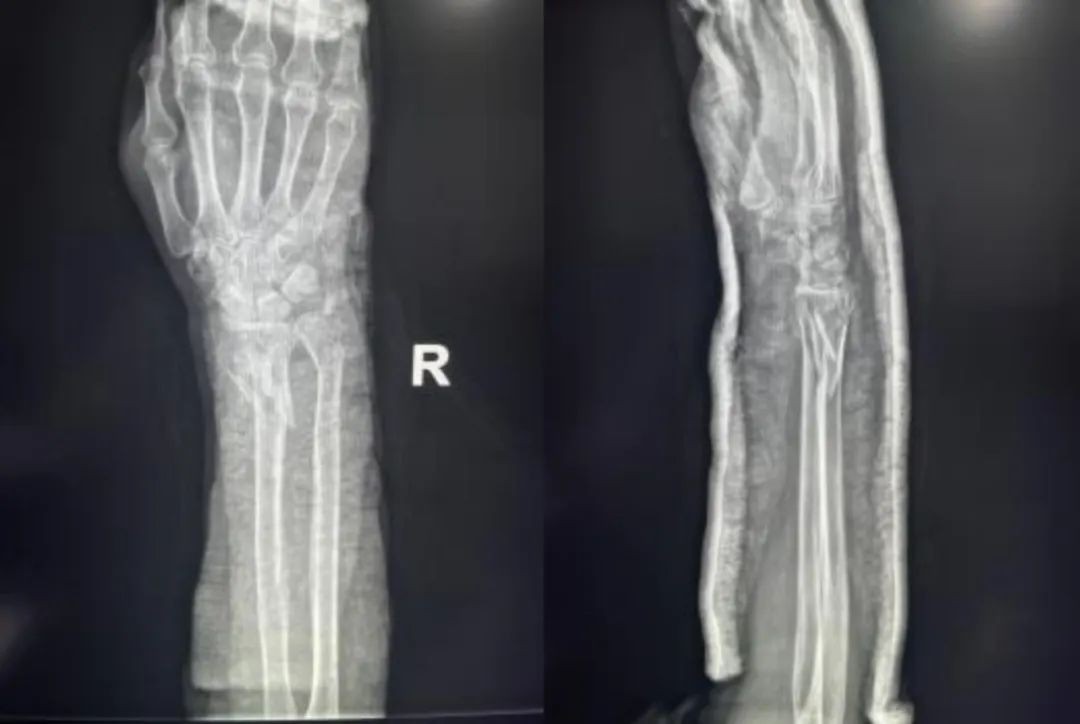

Opornice za zunanjo fiksacijo so uporabne za začetno ali dodatno zdravljenje pri specifičnih zlomih distalnega radiusa.

Zunanji fiksator nevtralizira aksialne napetosti, ki delujejo na distalni radius med kontrakcijo mišičnih skupin podlakti. Pritrditev je lahko čez zapestje ali pa ne ali pa je dodana dodatna fiksacija.

Vzporedni vlek ne obnovi popolnoma naklona dlani, vendar je nevtralni položaj sprejemljiv. Pooperativno je zapestje upeto v cevast mavec v rotiranem posteriornem položaju 10 dni, dokler bolečina in edem ne popustita.